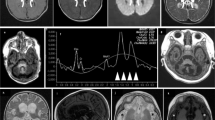

The boy reported here was the second child of healthy, first-grade consanguineous Turkish parents. His 13-year-old brother is healthy. Pregnancy was normal until the 27th gestational week when oligohydramnion was noticed. At that time the parents declined a recommended cesarean section. Finally, the child was born at 36 weeks of gestation by cesarean section due to anhydramnion. APGAR scores were 5/4/6, respectively. The neonate was small for gestational age with a birth weight of 1440 g, length of 39.5 cm and head circumference of 28.8 cm (all values below 3rd percentile). No dysmorphic stigmata were observed. During the immediate postnatal period the patient showed poor respiratory efforts, muscular hypotonia, bradycardia and generalized cyanosis. The child was intubated and transferred to the neonatal intensive care unit. Laboratory investigations revealed lactic acidosis (up to 22 mmol/l; norm: <1.8 mmol/l), requiring continuous buffering therapy with sodium bicarbonate. Cranial ultrasound demonstrated multiple choroid plexus cysts and symmetrical hyperechoic signal alterations in the basal ganglia, suggesting neonatal Leigh-like syndrome (Figure 1a). During the following 4 days, lactate levels remained elevated (up to 26 mmol/l) despite intravenous glucose infusion and buffering therapy. Laboratory investigations revealed elevated blood alanine (1088 μmol/l, norm <414 μmol/l) and massive lactic-acid excretion in urine. On the fifth day of life, slow improvement in acidosis was noticed with minimal lactate levels of 5 mmol/l. Respiratory efforts improved and the boy was extubated with adequate spontaneous breathing on the eighth day of life. However, the child showed reduced spontaneous movements with intermittent opisthotonus and muscle stiffness in the extremities. On the tenth day of life, the child suffered from seizures and recurrent episodes of apnea and bradycardia. The boy’s clinical condition further deteriorated and he died due to cardio-respiratory failure at 18 days of age. Because of a suspected mitochondrial disease, a skin biopsy was performed. Activity measurements of the oxidative phosphorylation enzymes in cultured fibroblasts showed a strongly reduced activity of respiratory chain succinate-cytochrome c oxidoreductase (complex II+III: 62 mU/UCOX, norm>160), pointing to a CoQ10 metabolism defect. Histological investigations of muscle and liver tissue were without specific findings.

(a) Brain ultrasound in a newborn with a pathogenic COQ9 variant. Left and middle panels: right and left parasagittal view, respectively, showing hyperechoic signal within the basal ganglia (arrow) and bilateral choroid plexus cysts (asterisk). Right panel: coronal view demonstrating symmetrical hyperechoic basal ganglia abnormalities suggesting a neonatal Leigh-like syndrome. (b) Schematic diagram showing the transcript generated in the presence of the c.521+1 deletion. Chromatogram shows that the deletion causes a skipping of exons 4 and 5 in the patient fibroblasts. (c) Western blotting on mitochondria-enriched fractions of patient and control fibroblasts (representative image). In patient cells no COQ9 is detected in the non-transduced condition (−). Signal is restored after lentiviral transduction with COQ9 wild-type cDNA (+). In addition, a COQ7 antibody was used, demonstrating a severe reduction of COQ7 protein in patient cells. Porin (VDAC) was used as a loading marker.